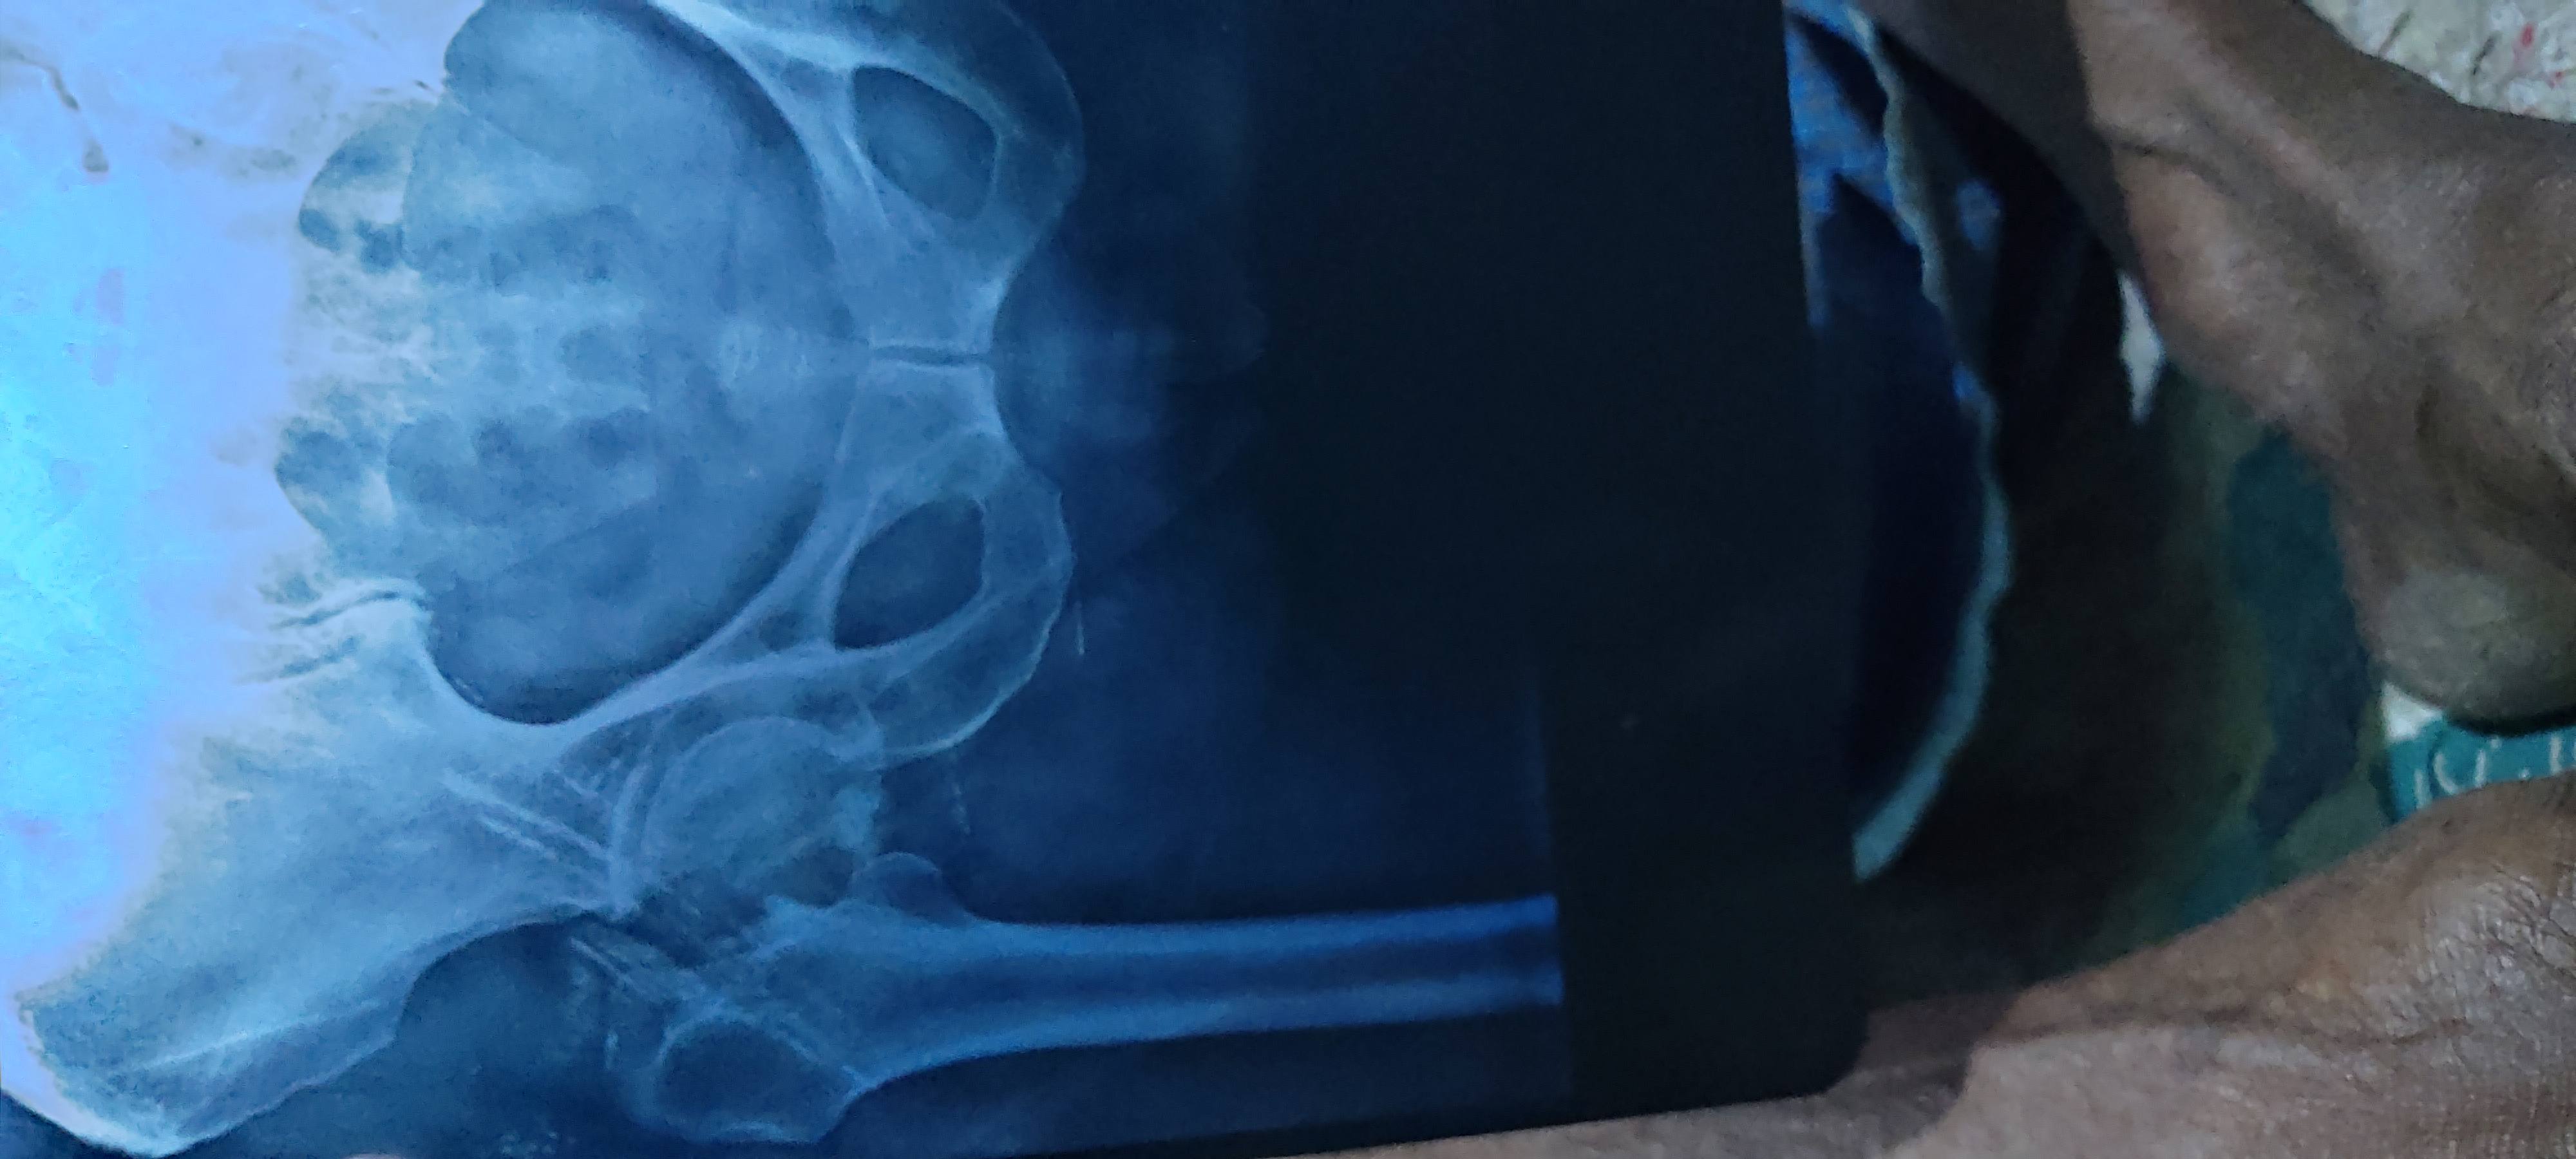

Md Taufik